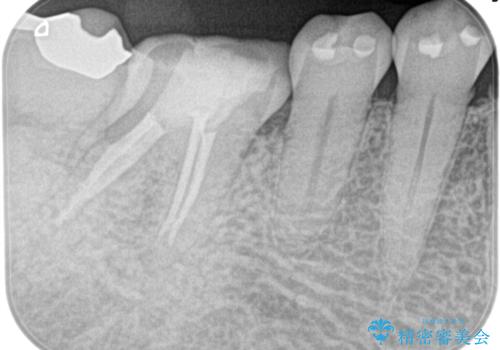

根管治療〜オールセラミッククラウン(エクセレント)の治療を行なっております。

根管治療後の最終補綴物は予後に大きく関わります。